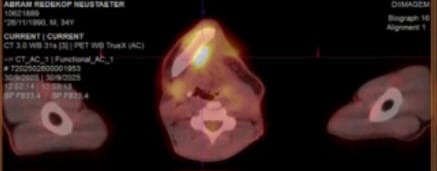

A new update on Abram He never got to implant his jawbone because he has three new tumors which you can find in the picture gallery. One on the other side jawbone, one on his chest one in his lung,He is now taking chemotherapy. in Brazil. ABRAM and his wife and family are in urgent need of our prayers and support. May God bless every prayer and support